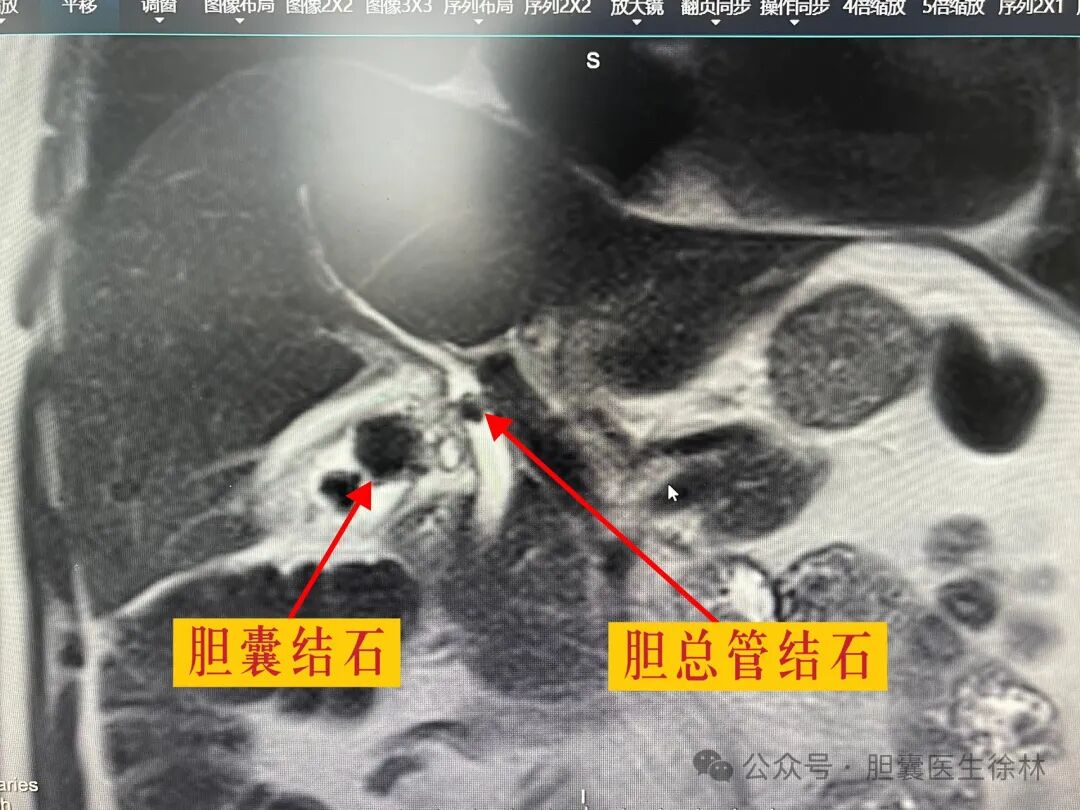

来我院后进一步行mri核磁发现大叔的胆囊多发结石并掉入胆管,是造成他腹部胀痛以及大便未解的真正原因。